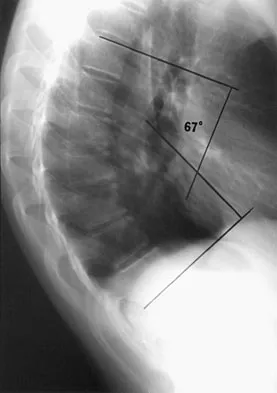

Question 43

Examination of a 13-year-old boy with asymptomatic poor posture reveals increased thoracic kyphosis that is fairly rigid and accentuates during forward bending. The neurologic examination is normal. Spinal radiographs show 10 degrees of scoliosis at Risser stage 2, and there is no evidence of spondylolisthesis. A standing lateral view of the thoracic spine is shown in Figure 41. The kyphosis corrects to 50 degrees. Management should consist of

Explanation